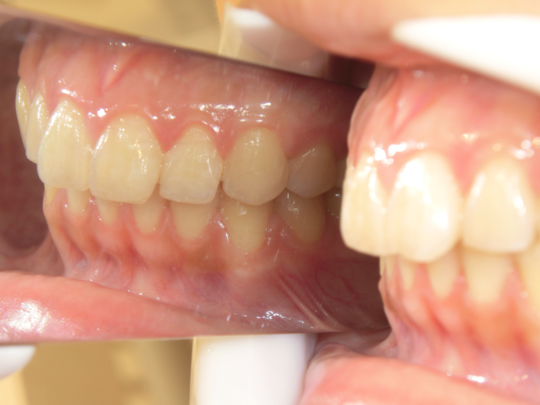

症例写真②

矯正前(正面)

矯正後(正面)

こちらの患者さまは、上下の前歯が離れていて、奥歯でしか噛めない「開咬(かいこう)」という状態でした。先天的な理由の場合もありますが、舌の癖や口呼吸などの悪い癖が原因でこのような歯並びになってしまいます。矯正後は、見た目が良くなっただけではなく、前歯でもしっかり食べ物を噛み切れるようになりました。

治療説明 歯科矯正でも目立ちにくい矯正方法です。透明に近いマウスピース型の矯正装置(アライナー)のため、歯に装着しても目立つことなく歯並びを矯正することが出来ます。また、一人ひとりの合わせて矯正装置を作製いたします。

治療期間 1年1か月

治療費用498000 円

治療の副作用(リスク)歯の動き方には個人差があり、予想された治療期間が延長する可能性があります。治療中は矯正歯科装置をつけるためハミガキを適切に行ってお口の中を常に清潔に保ち、さらに、かかりつけ歯科医に定期的に受診することが大切です。マウスピースの使用状況、定期的な通院など、矯正歯科治療には患者さんの協力が必要であり、それらが治療結果や治療期間に影響します。治療の経過によっては当初予定していた治療計画を変更する可能性があります。保定装置の装着時間が十分確保できない場合、歯並びや、咬み合せの「後戻り」が生じる可能性があります。